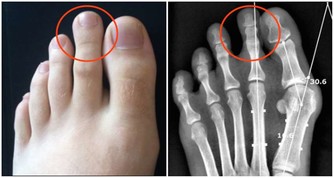

7.腿部的失調腳的血液循環不好,長時間的坐著會使血液循環變慢,會造成液體累積在腿部。

從腳踝腫脹和靜脈曲張到危險的血塊,這些問題稱為深靜脈血栓形成。